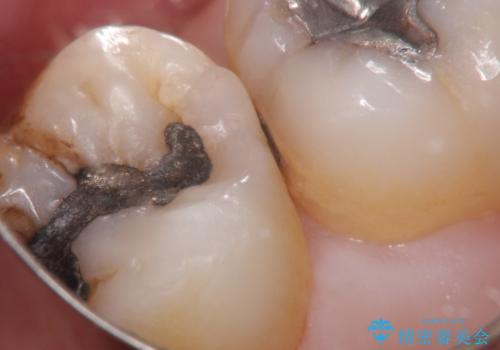

- 定期検診にて虫歯が見つかり、セラミックインレーに治療を行っております。

e-max プレスインレーにて修復治療を行っているため適合性及び審美性の高い治療を行うことができます